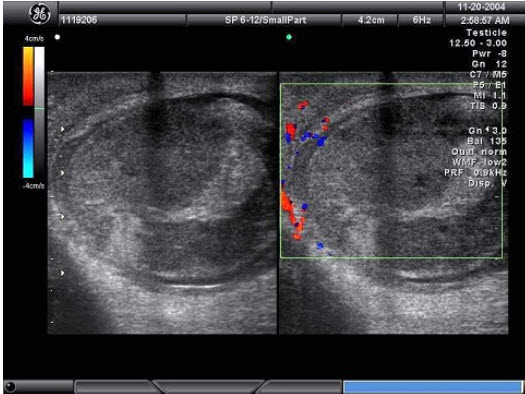

26、单项选择题

某男,因左阴囊疼痛不适数日,B超检查声像图如下,根据彩色声像图及血流特征,最可能的诊断为()

A.睾丸肿瘤

B.睾丸结核

C.睾丸炎

D.睾丸扭转

E.附睾炎